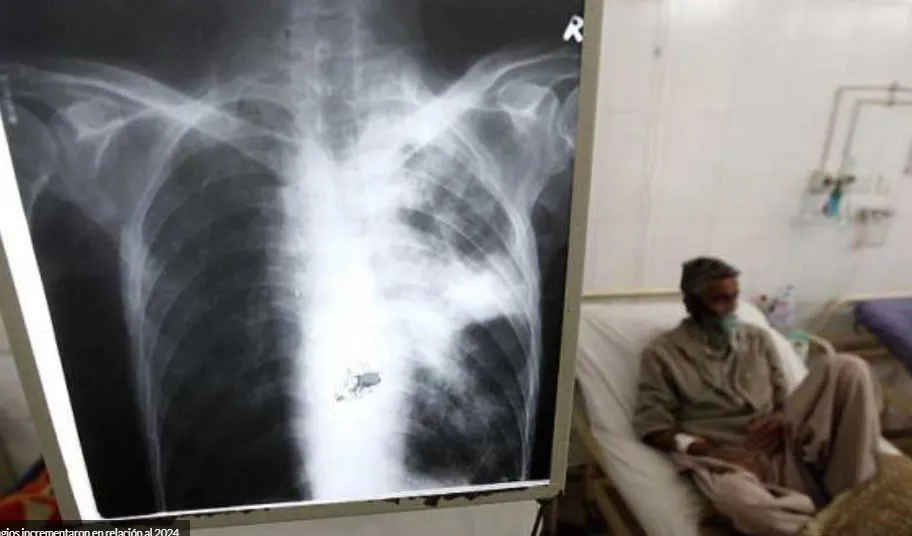

En 2024, Salta registró 967 nuevos casos de tuberculosis, 62 más que en 2023 y 115 más que en 2022. La enfermedad, que provocó 119 muertes en 2023, sigue siendo una preocupación sanitaria.

El Ministerio de Salud Pública informó que el 59% de los casos corresponden a varones y el 41% a mujeres. Además, el 14% de los pacientes diagnosticados tiene menos de 19 años.

Las cifras revelan que la mayor cantidad de casos se concentra en el interior de la provincia (68%), mientras que el 32% corresponde a la capital salteña. También se detecton ocho embarazadas con la enfermedad y 14 casos de tuberculosis multirresistente.

Para combatir la enfermedad, la provincia intensifica la búsqueda activa de pacientes sintomáticos, el diagnóstico temprano y la prevención a través de la vacunación y la concientización. Los agentes sanitarios juegan un papel clave en la detección de nuevos casos.

El tratamiento es gratuito y debe cumplirse de manera estricta para evitar complicaciones. Desde el Ministerio recuerdan la importancia de la consulta médica ante tos persistentes para evitar la propagación del virus.